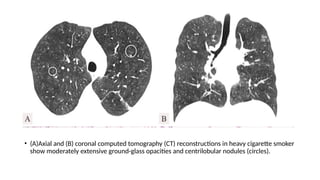

• (A)Axial and (B) coronal computed tomography (CT) reconstructions in heavy cigarette smoker

show moderately extensive ground-glass opacities and centrilobular nodules (circles).

• (A)Axial and(B) coronal computed tomography (CT) reconstructions in heavy cigarette smoker show moderately extensive ground-glass opacities and centrilobular nodules (circles).